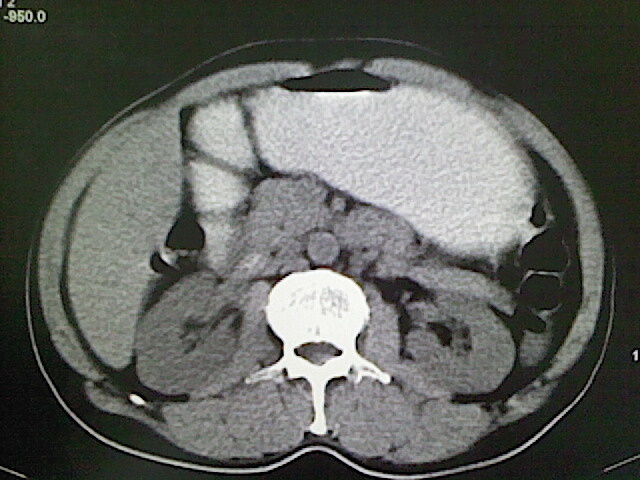

标题: CT18630:男,54岁,乙肝,大家看怎么样? [打印本页]

男,54岁,乙肝,大家看怎么样?

未见明显异常!(另:患者有乙肝病史,应定期做彩超检查!)

肝脏的要有增强敢说话

未见明确异常;建议必要时行ct增强扫描检查。